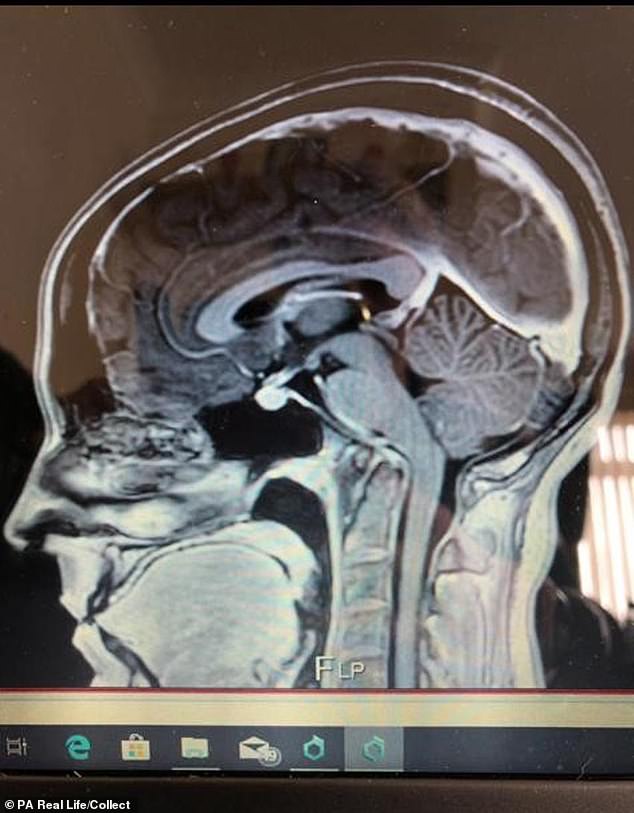

Ảnh chụp MRI cho thấy tình trạng mất ổn định đốt đội trục, cong xương sống, tràn dịch màng não của cô Pighills.

Các bác sĩ chẩn đoán cô Pighills bị mất ổn định đốt đội trục, cũng như bị cong cột sống, tràn dịch não và chèn ép thân não.